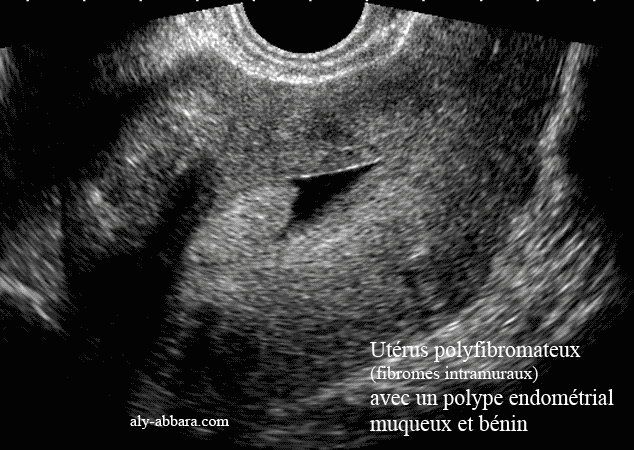

Utérus polymyomateux et porteur d'un polype endométrial muqueux bénin, pédiculé et asymptomatique, chez une femme âgée de 43 ans |

L'hydrorrhée qui peut être présente chez certaines femmes dont l'utérus est fibromateux, explique l'hypoéchogénicité occupant la cavité utérine et permettant la nette visualisation de son contenu, et sur cette coupe sagittale médiane de l'utérus, il été mis en évidence la présence d'un polype endométrial, muqueux, bénin, mesurant 22 mm de grand axe et 11 et 12 mm de petits axes (confirmation hystéroscopique et anatomopathologique). Le diagnostic échographique fut fortuit, lors d'un contrôle échographique pour douleur pelvienne en rapport avec une nécrobiose aseptique d'un myome de 5 x 5 cm de diamètre, intra-mural, invisible sur cette coupe sagittale médiane. |